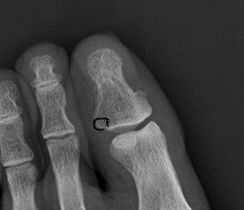

왼쪽 엄지발가락이 골절된지 3달이 좀 넘었습니다. 군인이여서 군병원에서 치료를 받았습니다 근데 왼쪽 엄지발가락을 스스로 움직여보면 움직일 수 있는 정도가 오른쪽 엄지발가락에 비해 훨씬 각도가 좁습니다. 그래서 손으로 움직여보면 다친부위에 살짝의 고통도 옵니다.. 어떻게 해야하죠 제가 군인이여서 xray는 보여드릴수 없고 제가 인터넷에서 가져온 사진에서 골절된 부분을 동그라미 친것입니다